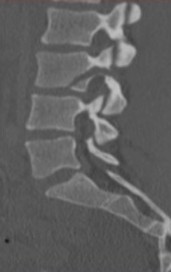

Coupe sagittale d’une fracture de chance au niveau de la troisième vertèbre lombaire.